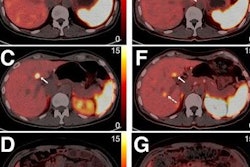

The researchers performed automated body composition analysis on 74 consecutive GEP-NET patients who had received whole-body gallium-68 (Ga-68) DOTATOC PET/CT exams as well as BIA and DEXA scans between February 2019 and October 2021. The deep-learning model was applied to the contrast-enhanced, 5-mm, whole-body CT images for all 74 patients.

The model examined seven volumes for different body compartments and quantified subcutaneous adipose tissue, visceral adipose tissue, intermuscular adipose tissue, epicardial adipose tissue, and paracardial adipose tissue. Muscular and bone tissue volumes were computed to generate a skeletal muscle ratio and body fat ratio.